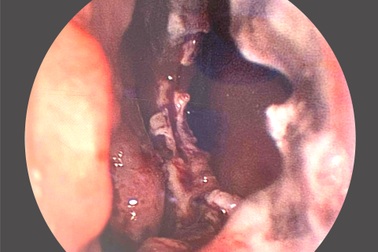

Nữ bệnh nhân bị hoại tử vách ngăn mũi vì xông thuốc không rõ nguồn gốcMột bệnh viện ở Bạc Liêu vừa phẫu thuật cho nữ bệnh nhân bị hoại tử vách ngăn mũi do sử dụng thuốc xông không rõ nguồn gốc.